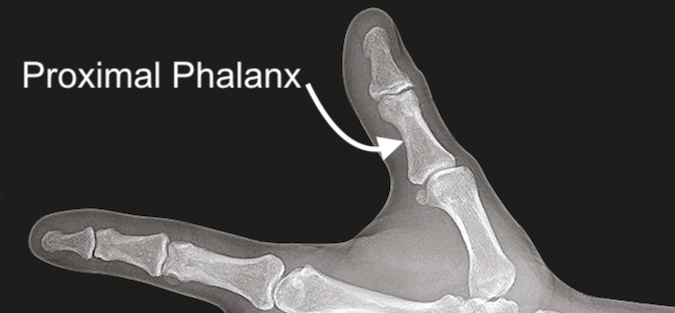

Thumb Proximal Phalanx Anatomy

Thumb proximal phalanx is the bone between the distal phalanx and the thumb metacarpal.

Note, there is no middle phalanx in the thumb.